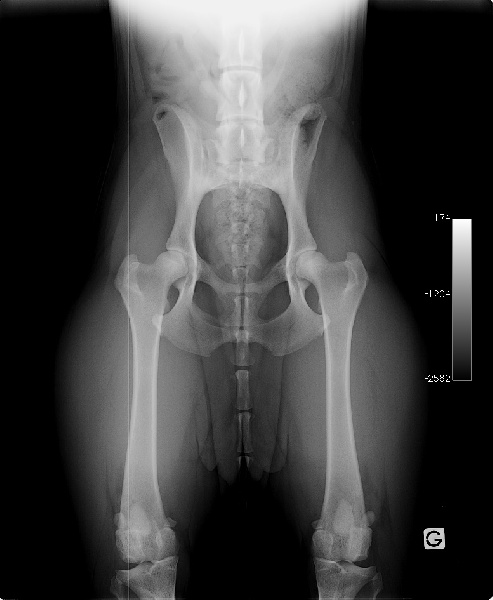

Dyspalsie A/A